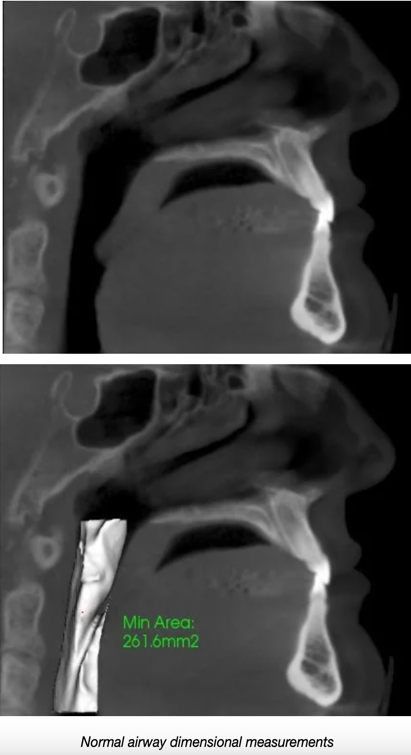

These are examples of normal and restricted airway volumes due to airway obstruction: